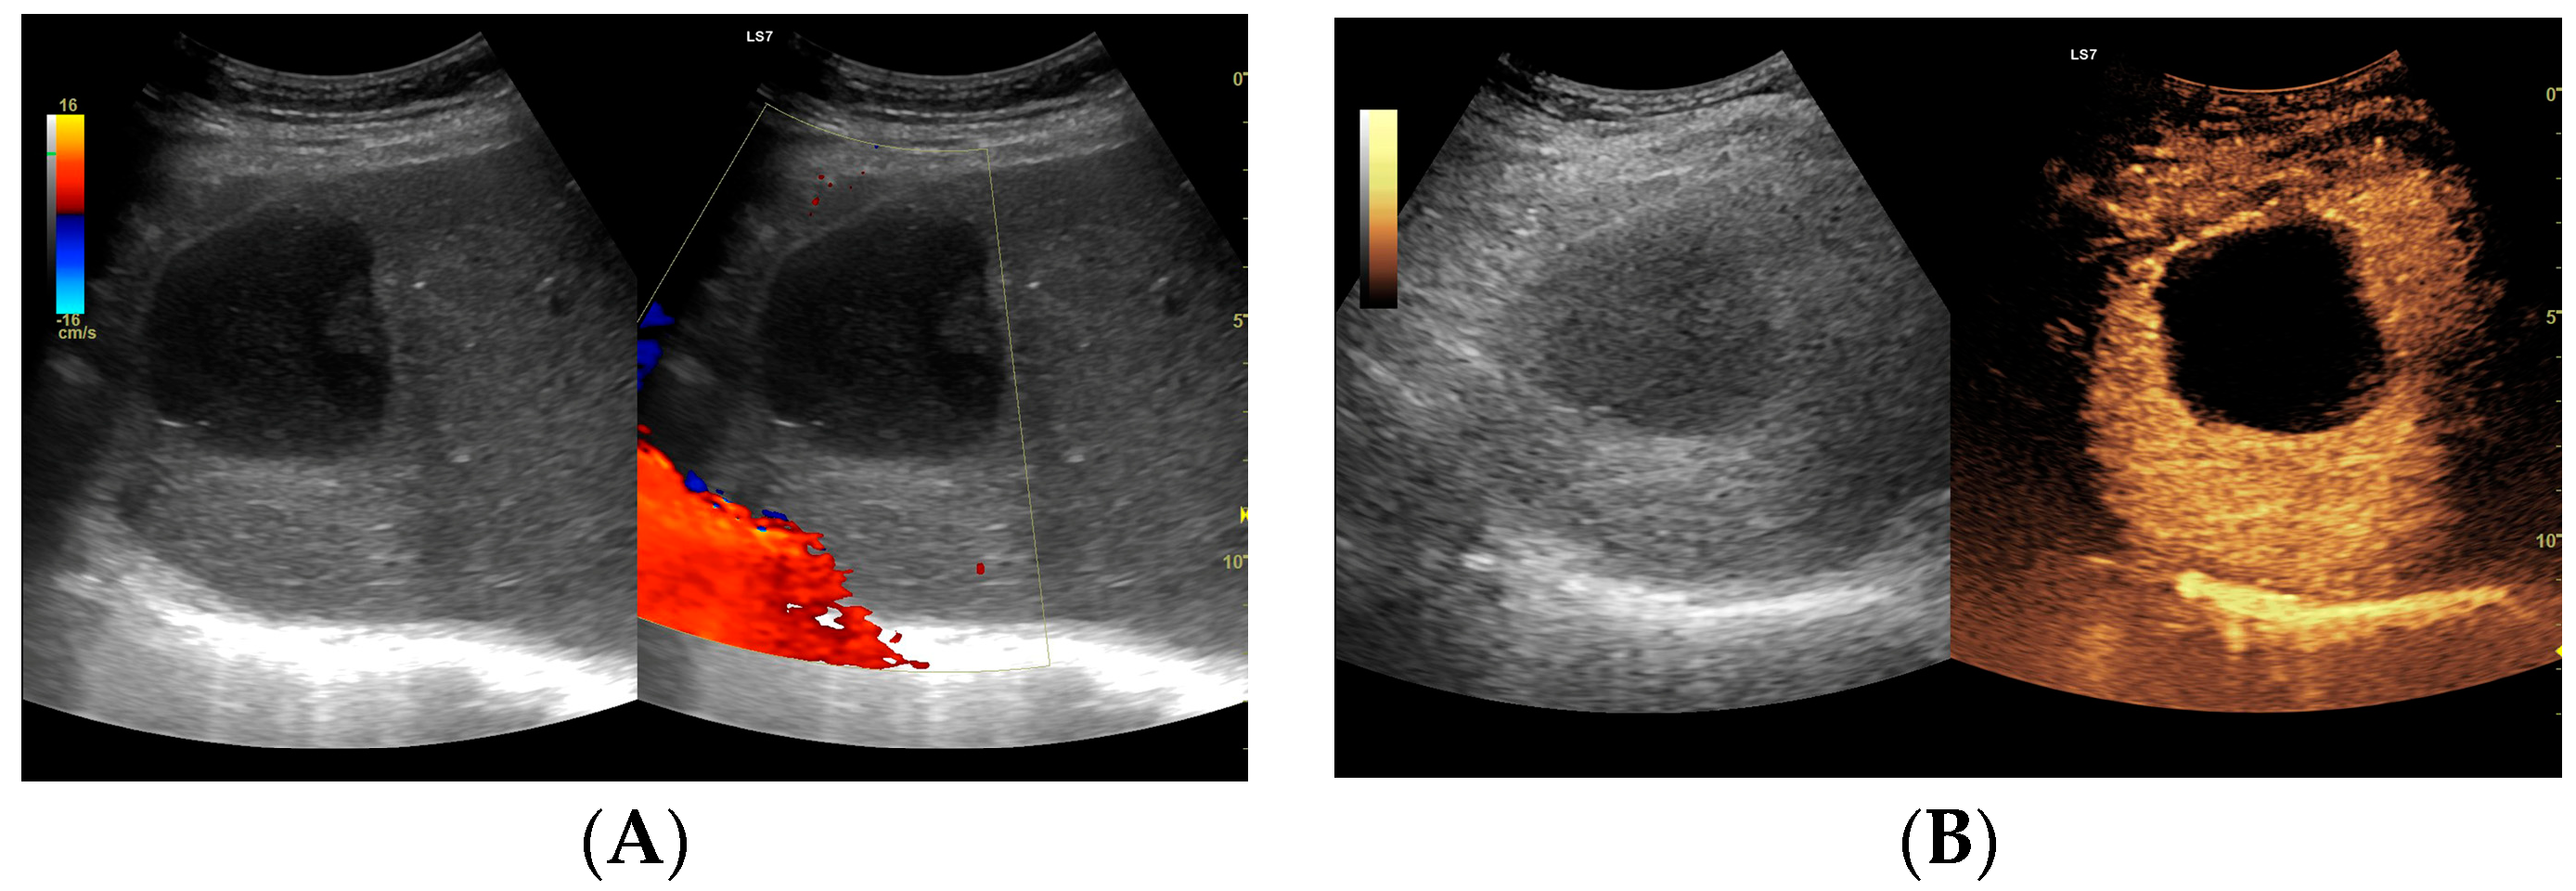

Figure 6.

(A) Ultrasound and color Doppler: The transverse view shows a focal lesion in the right liver lobe, identified as a type IV–, a cystic–like abscess, with a visible capsule in B-mode. In this case, it is possible to clearly classify the lesion as a type IV abscess and determine its actual fluid component. (B) CEUS arterial phase: The enhanced abscess capsule is visible. The total abscess was estimated to be 25.95 cm² from CEUS. The fluid component in CEUS overlaps with the B-mode image and measures 16.15 cm², so the volume is the same in both cases at 102.71 mL. The enhancement of the abscess capsule is slightly higher than that of the parenchyma. The lesion remains in the active phase of inflammation, although with less intensity.